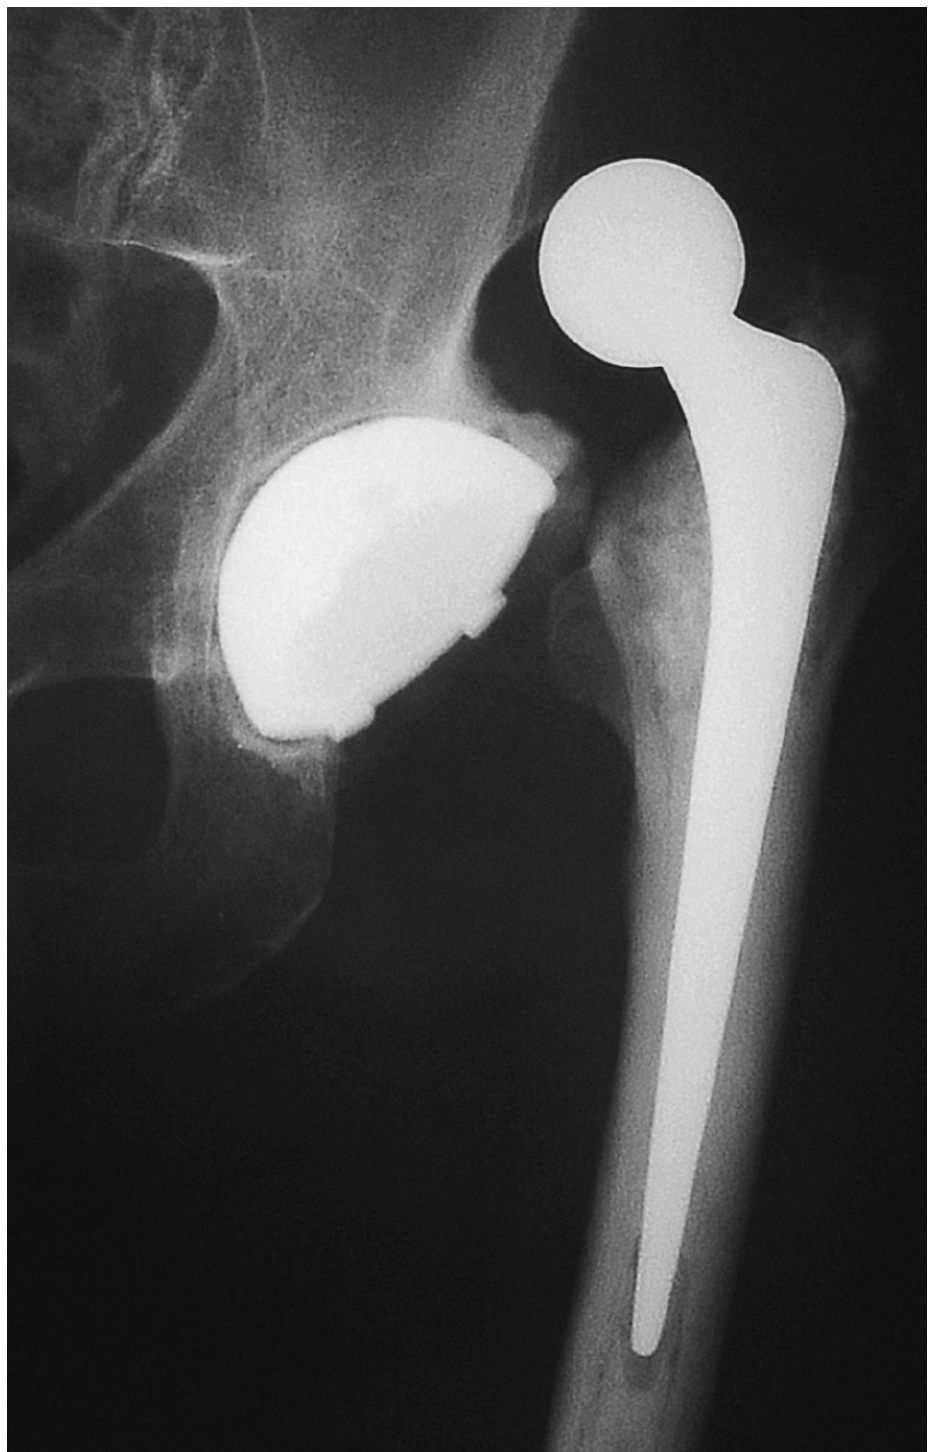

Los primeros se caracterizan además porque la cabeza protésica se encuentra más penetrada de lo normal y por consiguiente, al no disponer de ningún mecanismo de estrangulación, son los que determinan menor constricción (figs. 8, 9 y 10).

Una complicación no frecuente es la disociación cono-cabeza, siendo necesaria la reducción abierta y aumentar la longitud del cuello con o sin faldón (fig. 11).